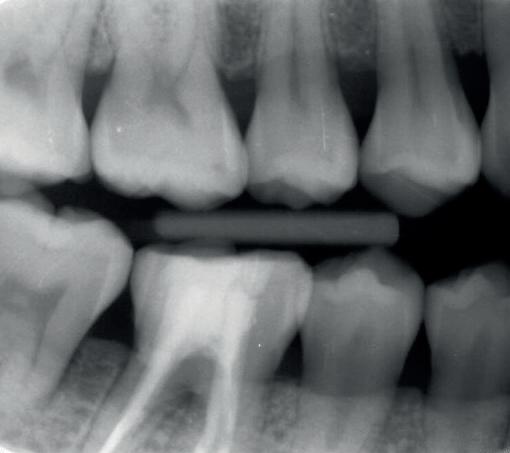

heeft de nadrukkelijke wens om geen brugconstructie te krijgen. Om die reden is een etsbrug of een conventionele brug geen optie. Daarom bestaat het behandelvoorstel uit vier losse kronen waarvan de 22 implantaat gedragen zal zijn. Een gedetailleerd onderzoek van de regio 22 is noodzakelijk (foto 4-6).

Uit het röntgenonderzoek blijkt dat op de locatie van de 22 veel bot verloren is gegaan en dat er niet direct een implantaat geplaatst kan worden. Om die reden is een botaugmentatie geïndiceerd. Wel zijn distaal van de 21 en mesiaal van de 23 de botpieken aanwezig die de papillen ondersteunen. Naast te weinig bot, is op de locatie 22 in bucco-linguale richting ook te weinig volume gingiva aanwezig. Daarom zal er tevens een soft tissue graft aangebracht worden. Tijdens deze behandeling wordt ook de recessie op de 23 zoveel mogelijk bedekt (foto 7 en 8).

Na vier maanden wordt er een CBCT gemaakt om het botvolume te kunnen beoordelen en een digitale planning te kunnen maken voor het plaatsen van het implantaat. Tevens wordt de stabiliteit van de botpieken op het buurelementen bekeken (foto 15 en 16).

Tijdens het verwijderen van het membraan is het botvolume klinisch waarneembaar en blijkt dat er voldoende bot is om het implantaat te kunnen plaat-